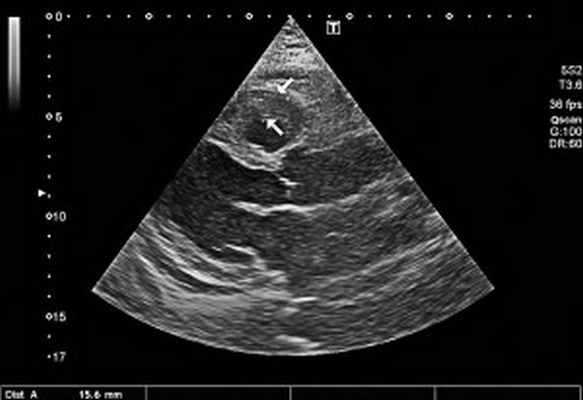

Рис. 2. Неравномерное значительное утолщение стенок ПЖ (парастернальный доступ, позиция по длинной оси)

ЭхоКГ: Патологические изменения миокарда ПЖ с утолщением стенок до 18 мм. Диффузный гипокинез стенок ЛЖ с дискинезом верхушки – ФВ 44%. В области верхушки ПЖ – наслоения между листками перикарда. Небольшое количество жидкости в полости перикарда – по ЗСЛЖ до 5 мм. Таким образом, в динамике на ЭхоКГ наблюдалось снижение сократительной функции ЛЖ на фоне его гипертрофии и, несмотря на проведенную высокодозовую терапию гормонами, не уменьшилась гипертрофия ПЖ.